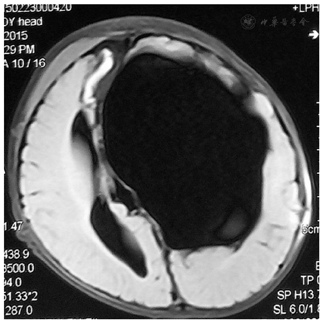

男,五周大婴儿,因"头围增大、吐奶一月余"就诊,行头部磁共振(Magnetic resonance imaging, MRI)检查示左侧额颞顶部巨大蛛网膜囊肿(Arachnoid cyst, AC),中线偏移,脑组织严重受压,伴有脑积水;

男,五周大婴儿,因"头围增大、吐奶一月余"于当地人民医院就诊,前囟门压力高,右侧肢体活动较对侧差,行头部磁共振检查示左侧巨大蛛网膜囊肿,遂来我院进一步治疗。入院后行蛛网膜囊肿腹腔分流术,定期复查头部磁共振可见囊肿进一步缩小,囊肿内分隔、透明隔存在,22月后再次入院行内镜下囊肿分隔和透明隔造瘘术。

MRI检查示左侧额颞顶部巨大蛛网膜囊肿,脑组织严重受压,伴有脑积水,2014-12行蛛网膜囊肿腹腔分流术,初始开放压力设定为18 cmH2O,后每间隔3-6月调低2-3 cmH2O;术后2月MRI发现蛛网膜囊肿缩小;术后22月MRI发现囊肿进一步缩小,可见囊肿内分隔,入院进一步行内镜下囊肿分隔和透明隔造瘘术,术后逐步将分流阀压力9cmH2O调至15cmH2O;